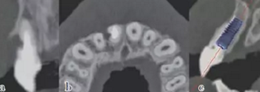

術(shù)前拍攝錐形束CT并做種植方案規(guī)劃。從圈紅處可以看出頰側(cè)骨組織不夠致密,建議備完孔后再做小翻瓣以觀察窩洞頸部的情況,圖2中的粉紅色及藍(lán)色HU值曲線顯示種植體內(nèi)部及其周圍的骨密度不高,為四類骨質(zhì),因此術(shù)中應(yīng)通過控制備孔的直徑或深度,以使種植體獲得較佳的初期穩(wěn)定性。

圖2 種植方案的規(guī)劃:a.頰舌側(cè)方向的截面圖,頰側(cè)圈紅處骨質(zhì)較疏松;b.近遠(yuǎn)中方向截面圖;c.種植體周圍的骨密度